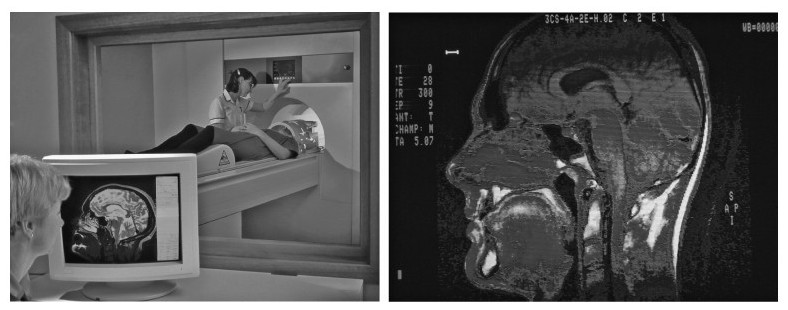

你也许会好奇科学家是怎样了解脑功能的以及脑的哪些结构负责人类的能力和活动。在早期,这样的信息来自意外的受害者和手术的幸存者(如H.M.),这些人让我们了解到特定的脑部位受损或切除之后会出现哪些功能的缺失。最近,脑成像(neuroimaging)技术加速了人们对脑的结构和功能的理解。例如CT或CAT扫描(计算机轴断层扫描)和MRI(磁共振成像)提供了静态成像如通过拍照探测受伤或损坏的区域。CAT扫描,是给患者注射一种放射性染色剂,然后用专门的X射线装置从不同角度为脑照相,这些计算机成像可创建脑的横断面图像。MRI使用射频波和强磁场来提供脑的高分辨率图片,它优于CT技术,因为它不需要使用放射性物质。射频波直接指向强磁场中的质子,质子被激发后被释放,发出无线电信号,这些信号被计算机加工形成图像。

CAT和MRI扫描,使用X-射线或无线电波扫描大脑,形成图像,来揭示脑的解剖结构。